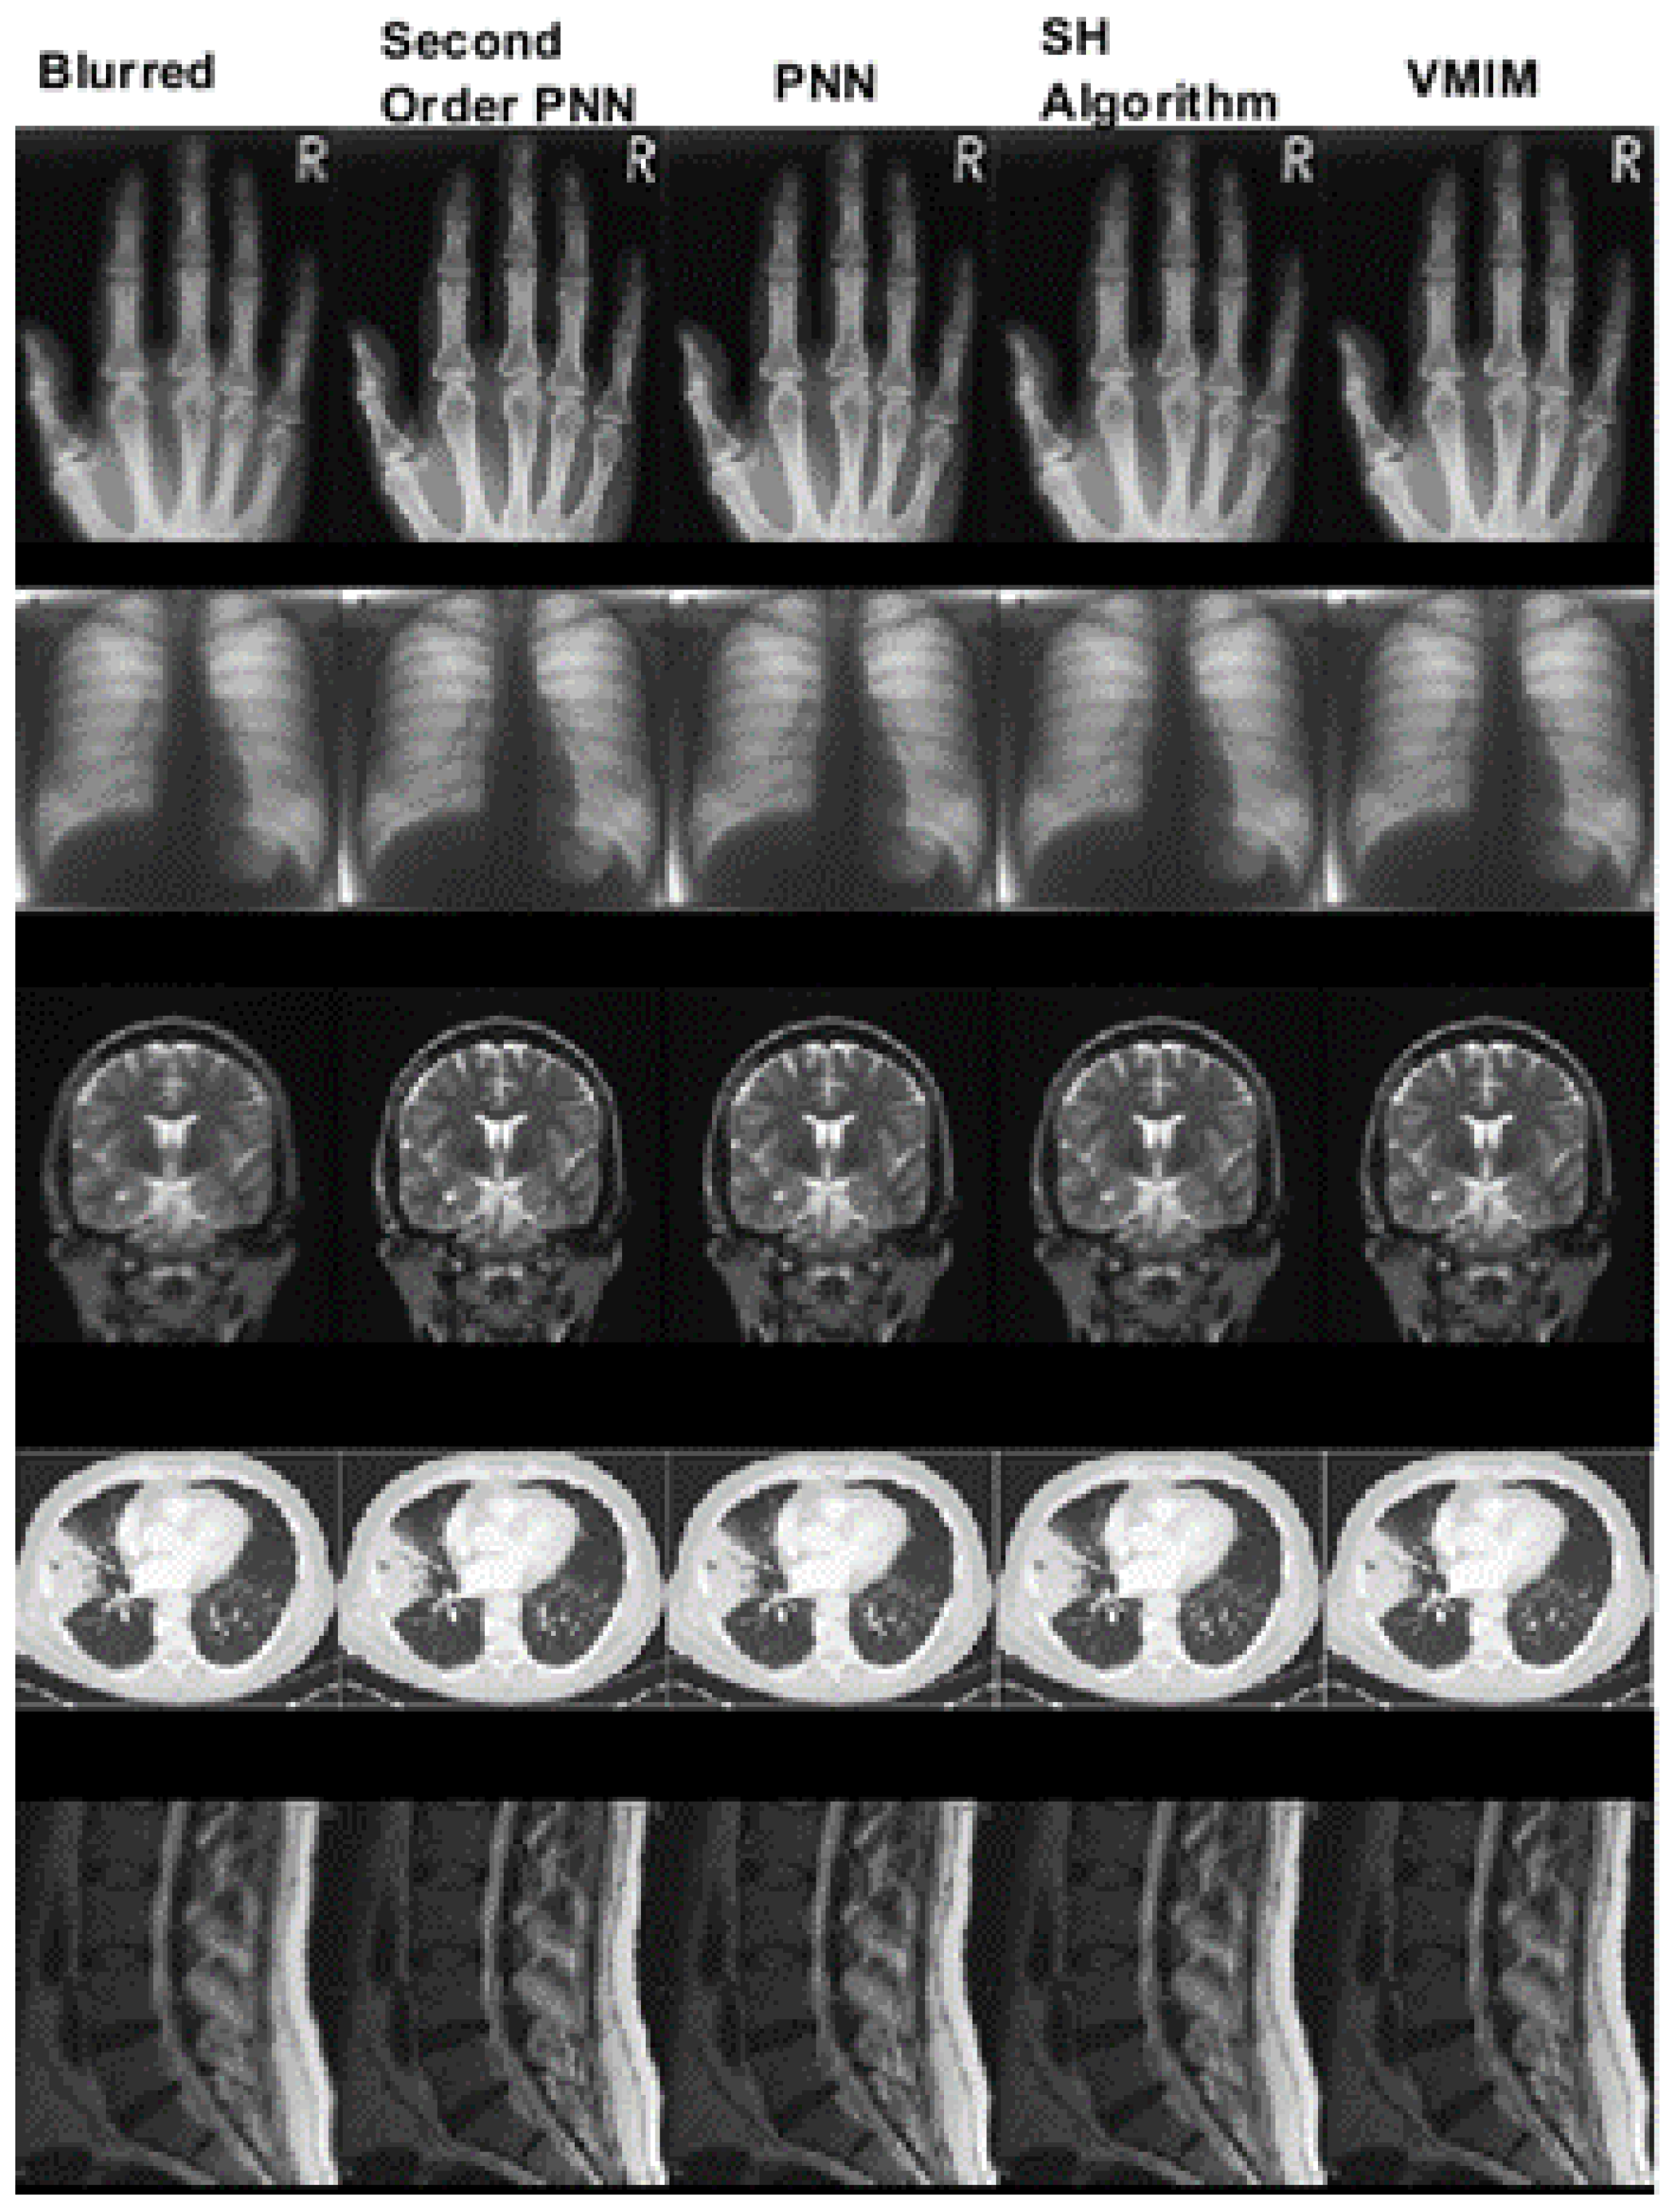

In Figure 3, we compare the second-order PNN with the PNN algorithm, SH algorithm, and VMIM. The second-order PNN is most effective in dealing with noised images.

Figure 3. Comparison of images recovered using different algorithms.

Mathematics 12 02360 g003

Table 3. Comparison of SSIM of the four algorithms.

SSIM

Second-Order PNNPNNSH AlgorithmVMIM

Hand X-Ray0.96120.87960.80190.8376

Chest X-Ray0.86390.83100.79160.8112

Brain MRI0.97490.90590.83960.8692

Lung CT0.98870.86710.80110.9032

Spine MRI0.94200.88830.80930.8881

Table 4. Comparison the SNR of images recovered using the four algorithms.

SNR(dB)

Hand X-Ray33.316528.331725.751426.9016

Chest X-Ray30.221829.059527.211728.2230

Brain MRI35.702629.700526.775928.0624

Lung CT37.485727.454025.660928.7853

Spine MRI33.076030.435627.858030.4226